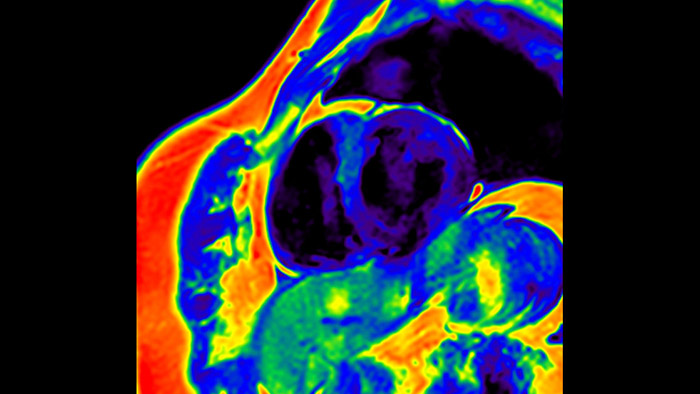

A utilidade do diagnóstico e prognóstico da RM cardíaca está a aumentar. Avalie a anatomia e função do coração utilizando aquisições cine, adquira informações sobre a perfusão e viabilidade do tecido cardíaco, visualize potenciais edemas com sequência de sangue escuro, aceda e quantifique mesmo a caracterização do tecido com a CardiacQuant.

O IntelliSpace Portal MR Caas7,8 Strain9 ajuda no diagnóstico e monitorização do paciente ao proporcionar parâmetros globais de deformação, tais como deformação longitudinal global (GLS), deformação circunferencial global (GCS) e deformação radial global (GRS), utilizando imagens de RM de eixo curto e longo, bem como descrevendo a deformação do miocárdio, como encurtamento, espessamento e alongamento durante o ciclo cardíaco.